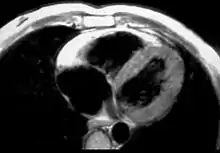

![]() صورة نسيجية لقلب مريض بالـARVD. صورة نسيجية لقلب مريض بالـARVD. | |

الرنين المغناطيسي القلبي Cardiac MRI

تشاهد التوضعات الشحمية في الجدار الحر للبطين الأيمن بصورة الرنين المغناطيسي القلبي. يكون الشحم عالي الكثافة في صور الـT1 weighted. بكل الأحوال، قد يكون من الصعب تمييز الشحم داخل العضلة القلبية والشحم في التأمور والذي يشاهد عادةً بالقرب من القلب. كما قد يكون من الصعب تمييز المنطقة تحت مثلث الشرف عن الثلم الأذيني البطيني، والذي يكون غنياً بالشحم.

يمكن للـMRI القلبي أن يظهر الرقّة الشديدة وانعدام الحركة akinesis في الجدار الحر للبطين الأيمن. بكل الأحوال، قد يكون الجدار الحر للبطين الأيمن الطبيعي بسماكة 3 مم، مايجعل من هذا الاستقصاء قليل الحساسية.